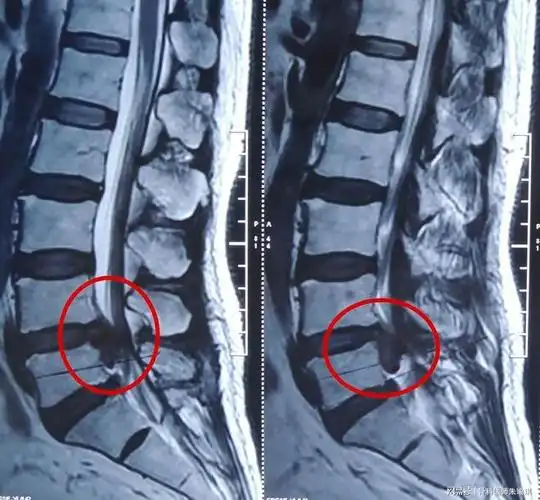

腰椎间盘突出症的症状,检查及治疗_腰椎间盘突出_症状表现_检查_治疗